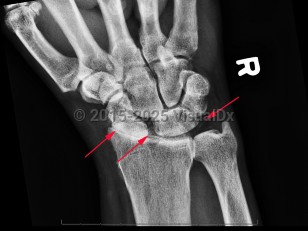

Calcium pyrophosphate deposition disease

CPPD disease usually affects patients 60 years and older and can have overlap with osteoarthritis. It affects women and men equally. Metabolic derangements such as hypophosphatemia, hypomagnesemia, and hypercalcemia increase the risk of CPPD. As such, conditions that predispose to metabolic derangements are associated with CPPD, such as hyperparathyroidism, hypothyroidism, Gitelman syndrome, hemochromatosis, and loop diuretic use. Similarly, inflammatory conditions of the joint can predispose to CPPD such as acute illness or joint trauma during the postoperative period, rheumatoid arthritis, and osteoarthritis.

The pathophysiology of pseudogout is not well understood, but CPP crystals forming in the cartilage is the first step in the disease process. Deposition of the CPP crystals affects the balance toward the production of pro-destructive prostaglandins and metalloproteinases, which destroy the chondrocytes and synoviocytes, cells that are important for the structural framework of cartilage and synovium.